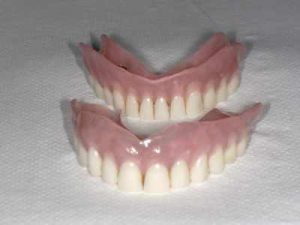

Jeśli nie jest możliwe wykonanie klasycznej odbudowy przy wykorzystaniu mostu protetycznego, który można oprzeć na stałych zębach pacjenta, stosujemy właśnie implanty, dzięki którym mocowanie protez ruchomych z bardzo dobrą stabilizacją jest możliwe. Już nawet dwa lub trzy implanty pozwalają na umocowanie protezy.